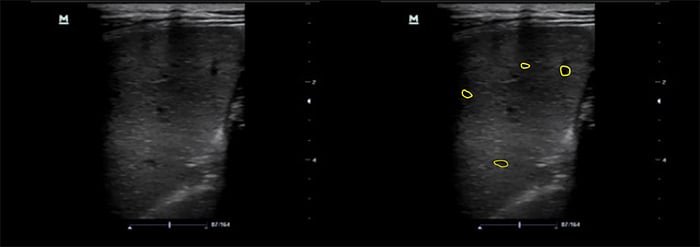

- Splenic micro abscesses: OR 1.921 (Figures 7 and 8, Videos 9 and 10)

- Micro abscesses will appear as small hypoechoic lesions. As they become numerous, they can coalesce and enlarge.

Figure 9. Spleen with microabscesses using linear transducer

- The use of a high frequency linear transducer can improve your ability to identify splenic micro abscesses. 21,26-8 Freezing the image and scrolling manually can slow the image down enough to identify small micro abscesses (Figure 8).